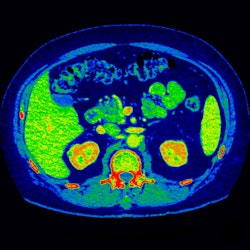

| Image acquired with GE's Gemstone spectral imaging technique displays MD iodine color map that suggests renal lesion enhancement. All images courtesy of GE. |

The technique uses what GE calls fast kVp switching, in which the kVp levels are switched with every other view -- a capability made possible by Gemstone detector material. A special viewing mode enables users to scroll through a stack of images to view different keV levels.

GE launched CT750 HD in 2008, touting the scanner's Gemstone detector design, which uses a garnet-based detector material. At this year's show, the company is rolling out Gemstone spectral imaging, a dual-energy imaging technique that's based on the Gemstone material.